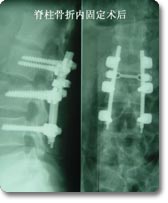

脊柱外科是该科的主要临床特色, 也是该科近年来发展的重点。在七十年代初就在国内率先开展了颈椎前路手术,大大拓展了新桥医院骨科脊柱手术治疗的范围,在全国享有较高的知名度。随后又积极开展了脊柱脊髓损伤的临床治疗和基础实验研究, 目前已治疗患者1000余例,其优良的治疗效果和精谌的手术技巧深得同行好评,使脊柱骨折复位成功率和截瘫的恢复率得到显著改善和提高。 |